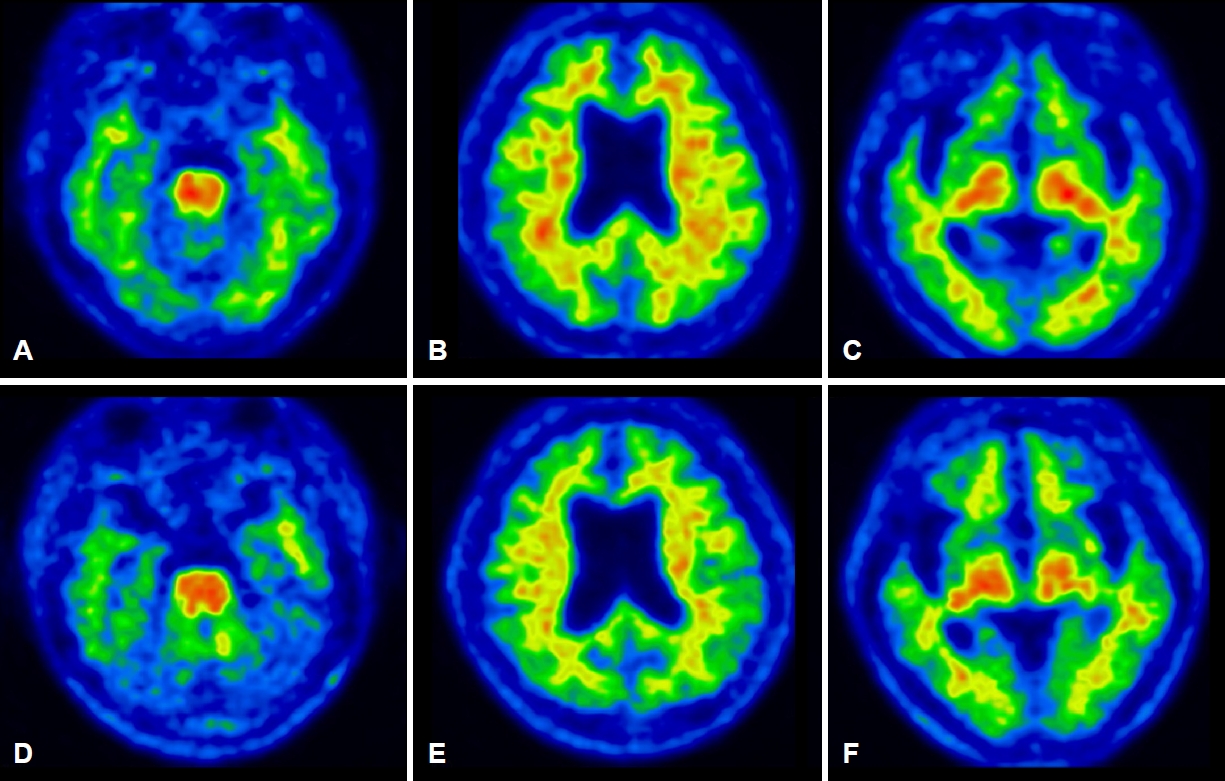

6년의 학력을 가진 오른손잡이인 61세 여자 환자가 서서히 시작된 기억력 및 언어능력저하로 지역 치매안심센터를 경유하여 2019년 6월 본원 신경과로 진료가 의뢰되었다. 한 달에 1-2번 정도 왕래하는 딸에 의하면, 환자는 약 1년 전부터 자신이 했던 일을 반복적으로 잊어버리는 경우가 많았고 물건의 위치를 기억하지 못하였다. 오래된 기억은 문제가 없었다. 그리고 대화할 때 단어를 쉽게 떠올리지 못하는 모습을 보였다. 길 찾기에는 문제가 없었고 성격 변화도 없었다. 집안 살림을 스스로 할 수 있었다. 과거병력과 치매 가족력에서 특이 소견은 없었다. 신경계진찰에서 운동, 감각 및 심부건반사는 정상이었다. 한국판간이정신상태검사(Korean-Mini Mental Status Examination, K-MMSE)는 17점, 임상치매평가척도(Clinical Dementia Rating, CDR)는 0.5점 그리고 임상 치매평가척도-총합점수(CDR-Sum of boxes, CDR-SB)는 1.5점이었다. 비문해노인특성반영 인지기능검사(Literacy Independent Cognitive Assessment)에서 나이와 학력에 비하여 기억력, 언어기능, 시공간기능, 집행기능 및 계산기능의 저하 소견이 관찰되었다. 뇌 자기공명영상(magnetic resonance imaging, MRI)에서는 전두측두엽과 해마의 위축이 관찰되었는데 우측에서 더 명확한 변화가 관찰되었다(Fig. 1-A-D). 18F-flutemetamol 아밀로이드양성자단층촬영(PET)도 시행되었다. 18F-flutemetamol 주입 10분 후에 얻은 초기 동적영상에서는 우측 전두측두두 정엽의 기능저하 소견이 관찰되었으나(Fig. 2-A-C) [4,5], 18F-flutemetamol 주입 90분 후 촬영한 지연 영상에서는 아밀로이드 침착이 보이지 않았다(Fig. 3-A-C; global standardized uptake value ratios, 1.33; cut-off value, 1.50). 뇌척수액에서 시행한 생물표지자 분석(INNOTEST ELISA kit; Fujirebio Diagnostics, Ghent, Belgium)에서 Aβ42 385 pg/mL (cut off value, 481 pg/mL), 총 타우(total tau) 524 pg/mL (cut off value, 326 pg/mL), p타우(p-tau)181 68 pg/mL (cut off value, 57 pg/mL)의 결과를 얻었다[6]. 뇌 PET검사에서 아밀로이드 축적을 보이지 않았으나, 환자의 임상 양상, 신경심리검사, 뇌 MRI, PET 초기 동적영상 및 뇌척수액생물표지자검사 결과를 종합할 때, 환자는 아밀로이드 양성, 타우 양성 및 신경변성 양성 상태의 조기발병 기억상실다중영역경도인지장애로 진단하였다. 환자는 검사 이후 1년 사이에 인지기능과 일상활동의 급격한 악화를 보였다. 환자는 전날 외식한 것을 기억하지 못하였다. 오후 3시에 남편에게 저녁을 먹으라고 차리기도 하였으며, 세탁한 것과 그렇지 않은 것을 구분하지 못하였다. 전혀 의사소통이 되지 않고 엉뚱한 행동을 하였다. 말을 할 때도 더듬거리면서 단어를 잘 말하지 못하였고 말수가 점차 줄어들었다. 집 근처에서조차도 방향을 헷갈려 하고 집안에서도 길을 헤매게 되었다. 금전 및 은행 업무는 전혀 할 수 없었다. 원래는 사교적인 성격이었으나 전혀 모임에 나가지 않았고 남편이 외출하면 불안해하였다. 반찬도 잘 못하고 하더라도 양이나 간 조절이 안되었다. 2020년 7월에 시행한 신경계진찰에서 운동, 감각 및 심부건반사는 정상이었다. K-MMSE는 13점, CDR은 2점, CDR-SB는 10점이었다. 뇌 MRI에서는 1년 전에 보이던 뇌위축이 더 진행된 소견을 보였다(Fig. 1-E-H). 18F-flutemetamol 아밀로이드 PET검사상, 초기 동적영상에서는 우측 전두엽과 양측 측두두정엽의 기능저하 소견이 관찰되었으나(Fig. 2-D-F), 지연영상에서는 여전히 아밀로이드 침착이 보이지 않았다(Fig. 3-D-F; global standardized uptake value ratios, 1.22). 환자는 이후로도 점차 악화되는 경과를 보여 2021년 4월에 시행한 검사에서는 K-MMSE 10점, CDR 2점, CDR-SB 11점을 기록하였다. 환자의 아포지단백질E (apolipoprotein E) 유전자아형은 ε4/ε4였다. 가족력은 없었지만 조기발병 치매 환자에서 비전형적인 알츠하이머치매의 생물표지자 발현을 보여 시행한 유전자검사(targeted exome sequencing; Dxome, Seongnam, Korea)에서 아밀로이드전구단백질(amyloid precursor protein, APP), 프레세닐린-1 (presenilin [PS]-1) 그리고 프레세닐린 -2 (PS-2)에는 원인 유전자변이(causative gene mutation)가 없음을 확인하였다.

61세 여자 환자는 3년여에 걸쳐 기억장애를 포함한 여러 영역의 인지장애와 이로 인한 일상활동장애를 보였으며, 증상이 서서히 발생하여 지속해서 악화하였다. 뇌 MRI에서의 우측 전두측두엽의 뇌위축과 아밀로이드PET의 조기 동적영상에서 전두측두두정엽의 대사 저하 양상이 관찰되는 것은 감별진단으로 알츠하이머치매 외에 전두측두치매나 피질기저핵변성도 고려할 수 있다. 그러나 3년간의 임상 경과로 미루어 환자는 초기에 현저한 기억저하를 보였고, 두드러진 이상행동을 보이지 않았으며 운동질환과 관련된 신경계 이상을 보이지 않아 전두측두치매나 피질기저핵변성보다는 알츠하이머치매가 보다 적합한 임상진단명으로 생각되었다. 뇌척수액 검사에서는 Aβ42 감소, 총 타우 증가, p-tau181 증가가 관찰되어 알츠하이머병 병태생리 과정에 대한 증거가 생물표지자로 일치하는 소견이었으나 아밀로이드PET에서 음성이 관찰되었다. 환자는 PET-/CSF+ 알츠하이머치매의 가능성을 가장 높게 생각하였으나 1년 후 중기 치매 진행된 상태에서도 아밀로이드PET 결과가 여전히 음성으로 관찰되어 환자의 최종적인 진단명이 알츠하이머병인지 또는 알츠하이머병 외에 다른 병이 동반되어 있는지에 대해서는 뇌의 병리조직검사 결과가 뒷받침되어야 하는 제한점을 가진 증례이다.